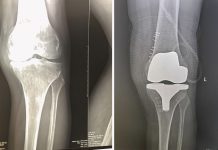

- В случае болезненного хруста или других проблем с суставами, важно обратиться к врачу. Комплексная реабилитация, включающая физиотерапию и лечебную гимнастику, может быть решающим шагом к восстановлению.